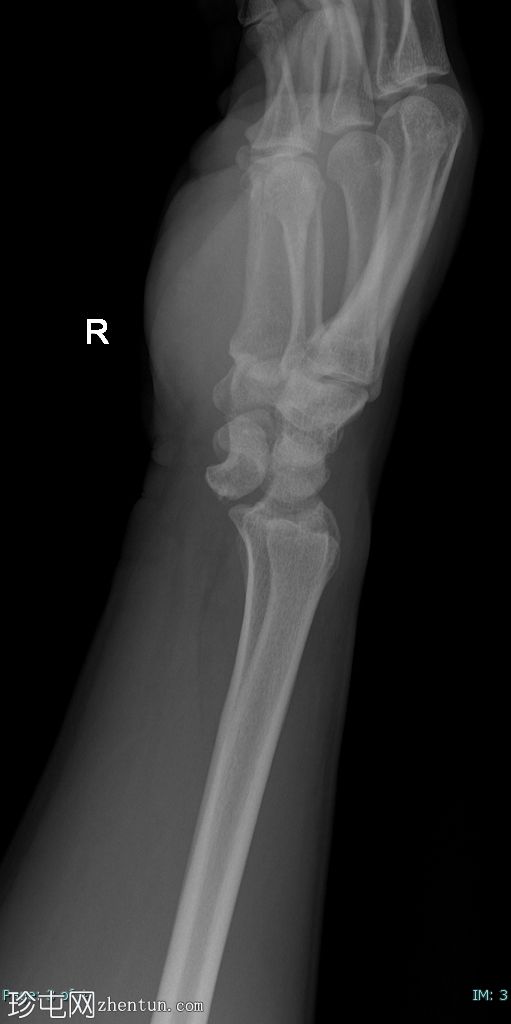

右腕

X线片

侧位片

月骨呈“饼状”移位,掌侧成角和移位,侧位片上呈“倾倒的茶杯”样外观。

侧位片上桡骨和头状骨对位正常。

尺骨茎突骨折移位。未见其他骨折。

腕关节处桡骨和尺骨对位正常。

软组织肿胀。